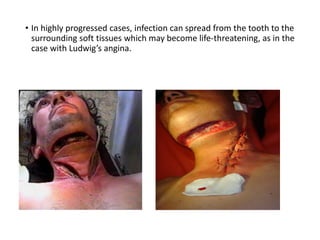

Dental caries, also known as tooth decay, is caused by certain types of acid-producing bacteria in the mouth that damage tooth structures when fermentable carbohydrates like sugar are present. It can lead to pain, tooth loss, infection, and in severe cases, death. While early signs may include white spots on teeth, untreated caries will form cavities. Risk factors include poor oral hygiene, frequent sugar consumption, dry mouth, and tobacco use. Treatment involves removing decay, restoring teeth, or extracting severely damaged teeth to prevent further destruction and infection. Preventive measures include proper brushing, flossing, limiting sugar intake, dental sealants, and fluoride therapy.